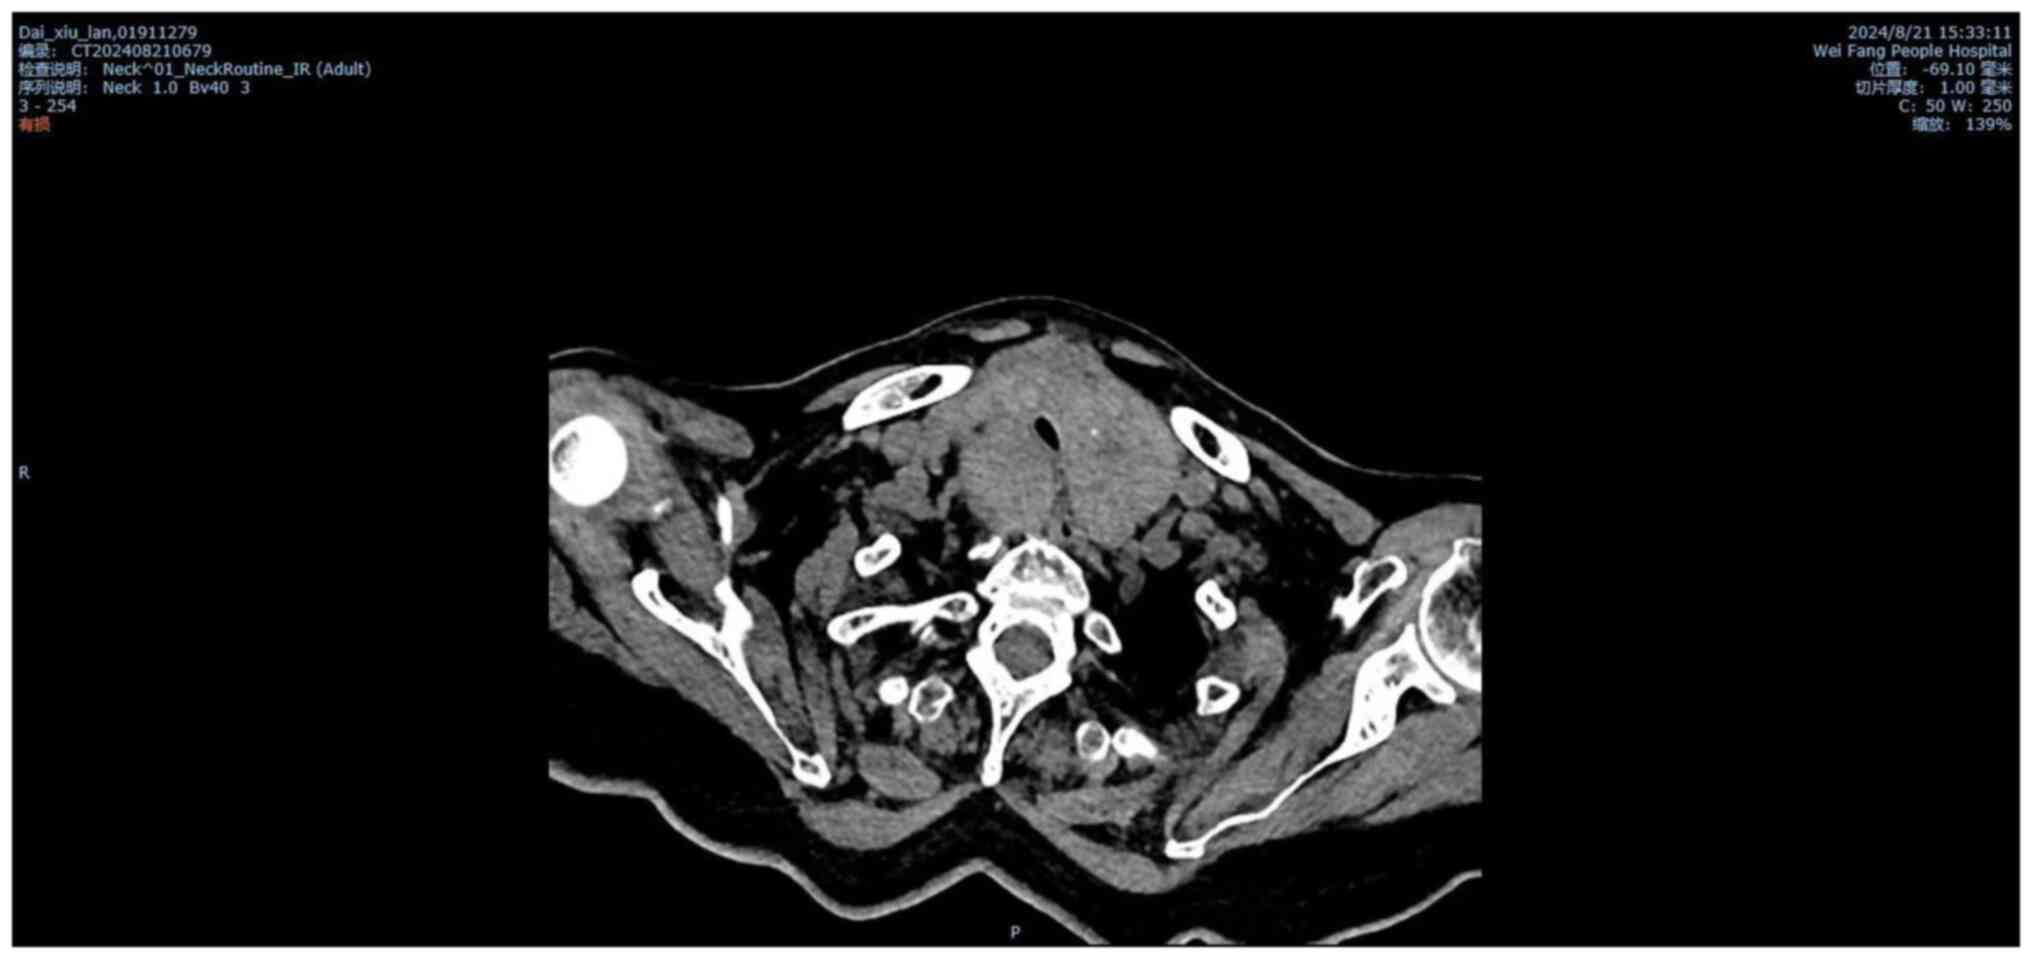

The electrocardiogram displayed marked sinus tachycardia. Neck CT images revealed an enlarged bilateral thyroid compressing most of the tracheal lumen, with the narrowest diameter of the stenosis being 4.6 mm (Fig. 1). CT scan of the brain and abdomen yielded normal results (data not shown).

Figure 1

CT scan demonstrating tracheal compression due to the large thyroid. Tracheal lumen diameter was compressed (4.6 mm) prior to surgery.